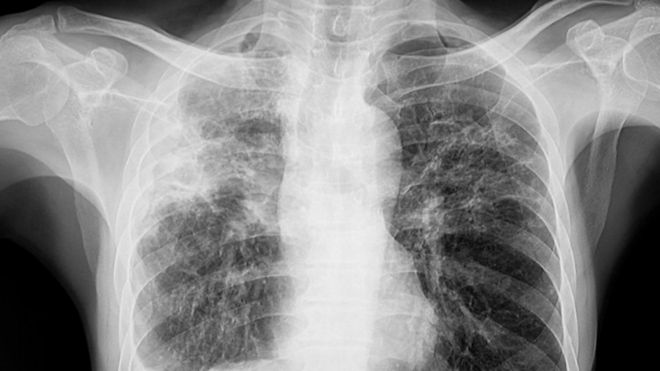

Para entender a perspectiva da cura da fibrose pulmonar, é fundamental compreender sua natureza. A fibrose pulmonar envolve a formação de cicatrizes no tecido pulmonar, que leva ao endurecimento dos pulmões e compromete a capacidade de trocas gasosas adequadas. Isso resulta em sintomas como falta de ar, tosse persistente e fadiga, afetando significativamente a qualidade de vida dos pacientes.